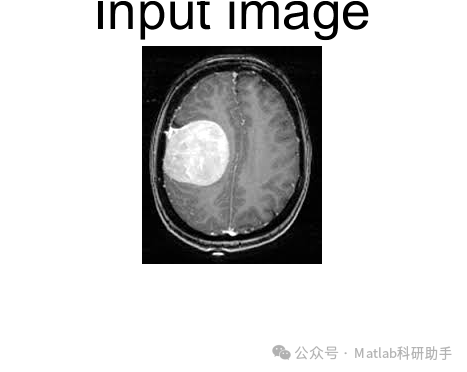

脑肿瘤是严重威胁人类健康的疾病之一,其早期、准确的检测和精确分割对于制定有效的治疗方案和提高患者生存率至关重要。近年来,随着医学影像技术的飞速发展,特别是磁共振成像(MRI)技术的进步,为脑肿瘤的检测和分割提供了强有力的支持。本文将深入探讨使用 MRI 图像进行脑肿瘤检测和分割的关键技术、挑战以及未来发展方向。

⛳️ 运行结果